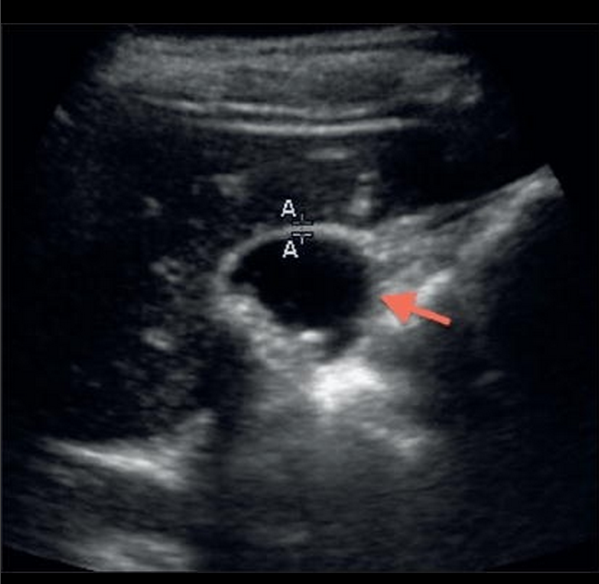

We report a case of superior mesenteric artery dissection found on emergent bedside ultrasound in a 46-year-old male complaining of abdominal pain with a history of cocaine abuse and prior aortic dissection. Bedside ultrasound in the emergency department revealed an intimal flap in the descending aorta with extension into the superior mesenteric artery prompting early surgical consultation before computed tomography because of concern for acute mesenteric ischemia.

Just one of their images is displayed below – but take a look at the video in JEM to truly see the awesomeness. A subscription and password is required, but it’s a great journal with lots of cool ultrasound cases published almost every month.